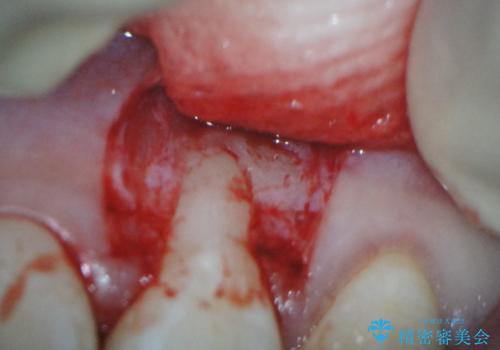

前歯の歯肉退縮 歯周形成外科(歯冠側移動術)

- 上顎左側側切歯の歯肉退縮を主訴に来院されました。

生活に支障はないが審美的要求が強く歯肉形成外科(歯冠側移動術)を行うこととしました。

根面被覆術には結合組織を用いる場合もありますが、今回のケースでは、角化歯肉が十分あり、審美性の要件が強いため、隣在歯との調和が取りやすい歯冠側移動術のみで対応しております。

結合組織を使用するメリットは術後の後戻りのリスクを減らすことが考えられます。